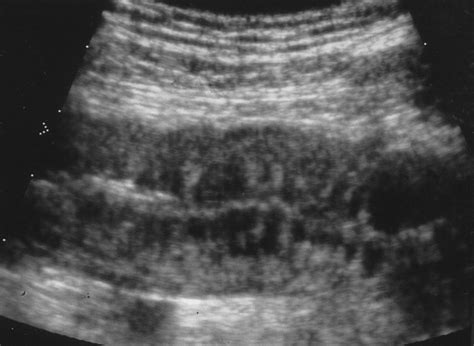

Radiologists identify this condition when they measure the intestinal wall and find it exceeds the standard parameters during diagnostic imaging. Because the gut is a complex system involving both the small and large intestines, this finding can occur anywhere along the digestive tract. It is important to remember that this is a symptom of an underlying process rather than a disease on its own.

- bowel wall thickening ultrasound

- bowel wall thickening radiology